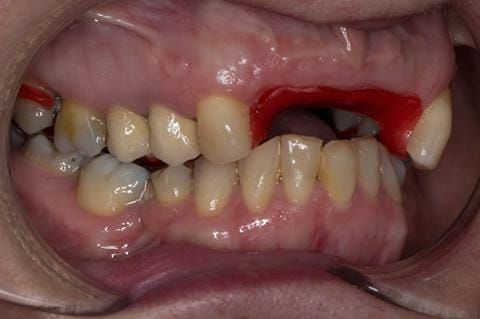

- UR2 peri-radicular periodontitis with a peri-radicular area on the root apex. Retrograde amalgam filling from a previous apicectomy. No visible root canal or root canal filling. Large circumferential marginal gap between the crown and tooth. Large post and core present. Very little tooth structure remaining resulting in a fragile tooth with increased potential for fracture.

- UR1 peri-radicular periodontitis with a small peri-radicular area on the root apex with wide blunderbuss apex. Radio-opaque root canal filling present approximately 3 mm short of the radiographic apex. Large circumferential marginal gap between the crown and tooth. Large post and core present. Very little tooth structure remaining resulting in a fragile tooth with increased potential for fracture.

- UL1 peri-radicular periodontitis with a peri-radicular area on the root apex. Retrograde amalgam filling from a previous apicectomy. Visible root canal space with no sign of root canal filling. Large circumferential marginal gap between the crown and tooth. Large post and core present. Very little tooth structure remaining resulting in a fragile tooth with increased potential for fracture.

- UL2 peri-radicular periodontitis with a peri-radicular area on the root apex. No visible root canal or root canal filling. Large circumferential marginal gap between the crown and tooth. Large post and core present. Very little tooth structure remaining resulting in a fragile tooth with increased potential for fracture.

- High smile line showing gum above gingival zeniths of upper front teeth when smiling. Aesthetic failure of the upper four incisors with inflammation of the gingivae and mis-match of the gingival zenith levels.